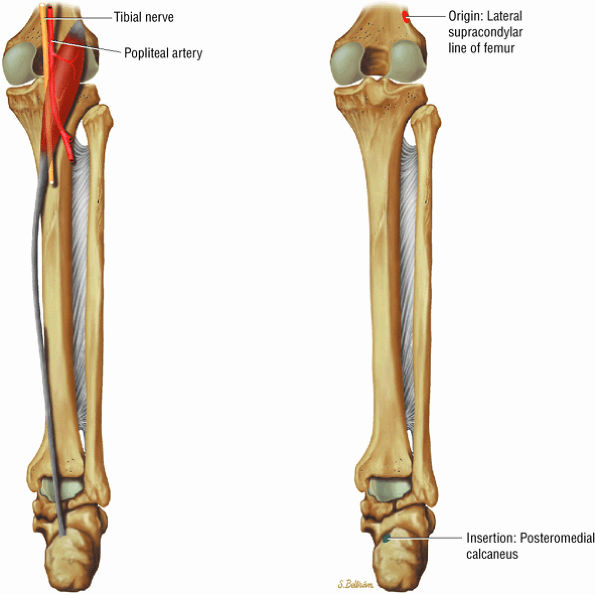

The posterior muscles of the leg include a superficial group and deep group. The superficial group is represented by the gastrocnemius (Fig. 5.6), the soleus (Fig. 5.7), and plantaris (Fig. 5.8).

The deep group of posterior leg muscles comprises the popliteus (see discussion in Chapter 4 on the knee), the flexor hallucis longus (Fig. 5.9), the flexor digitorum longus (Fig. 5.10), and the tibialis posterior (Fig. 5.11).

FIGURE 5.8 ● PLANTARIS The plantaris plantar flexes the foot and is visualized as a 2- to 3-mm hypointense dot-like structure on axial images anteromedial to the Achilles tendon. The plantaris tendon courses obliquely between the gastrocnemius and soleus muscles.

FIGURE 5.9 ● FLEXOR HALLUCIS LONGUS The flexor hallucis longus (FHL) flexes the great toe and plantarflexes the foot. The FHL is susceptible to injury during extremes of ankle plantarflexion and metatarsophalangeal dorsiflexion. The proximal sheath, 10 to 12 cm in length, has no mesotenon and may communicate with both the ankle joint and the sheaths of the flexor digitorum longus and tibialis posterior.